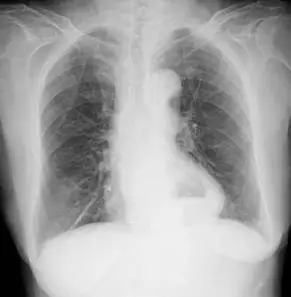

病人主訴胸骨後和上腹部疼痛且食慾不佳,胸部 X光檢查呈現如圖,下列那一項診斷最正確?

本張胸部 X 光(正面 PA view)可見以下重要發現:

心後區(Retrocardiac region)異常:在心臟影後方(左下縱膈),可見一明顯的圓形/橢圓形緻密影,合併有氣體陰影(air-fluid level)。此為典型的胃或腸段從腹腔疝入胸腔、經橫膈食道裂孔所形成的影像特徵。

縱膈(Mediastinum):縱膈寬度正常,無明顯增寬,不支持主動脈剝離(aortic dissection)的典型表現。

肺野(Lung fields):雙側肺野清晰,無明顯浸潤或氣胸表現,不支持氣縱膈(pneumomediastinum)的診斷。

橫膈上方氣泡影:在橫膈水平線上方可見含氣體結構,此影像強烈提示胃泡(gastric bubble)移位至胸腔。

整體影像與大型食道裂孔疝氣(sliding type 或 paraesophageal type)之典型胸部 X 光表現一致:心後區氣液面(retrocardiac air-fluid level)為最重要的診斷線索。